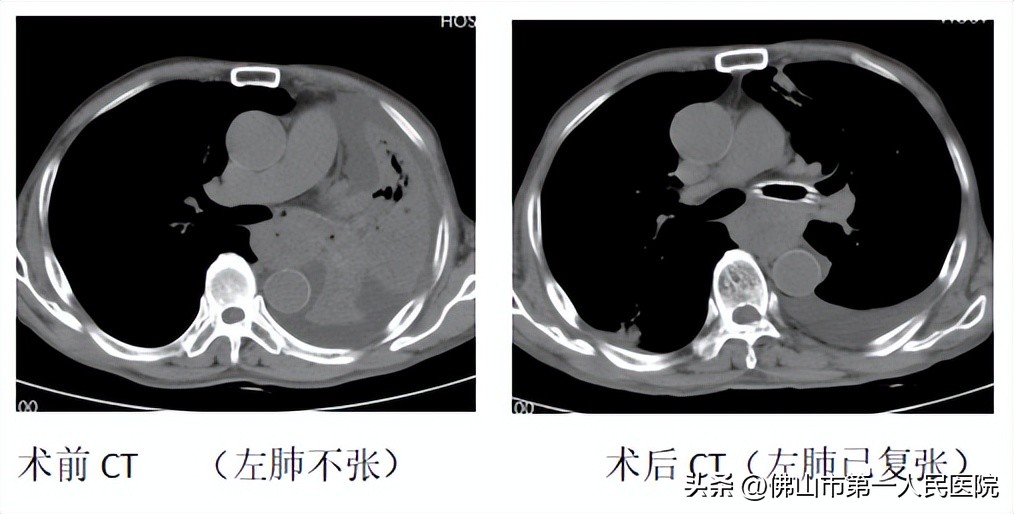

手术当日,在麻醉科刘洪珍主任精心配合下,张培芳主任带领魏晓群主治医师为苏伯进行了气道综合介入治疗。张培芳置入纤支镜,先后予电刀、一次性电圈套器、活检钳等,将这气道“拦路虎”取掉,再快速置入一次性金属覆膜支架,让原本完全闭塞的气道重新通畅。术后苏伯恢复良好,第二天已能够下地活动,原本呼吸困难的感受一扫而光,高热也很快退下来了。复查胸部CT原本压缩的肺部已复张。苏伯和家属对此充满感激之情,喜悦之情洋溢在脸上。